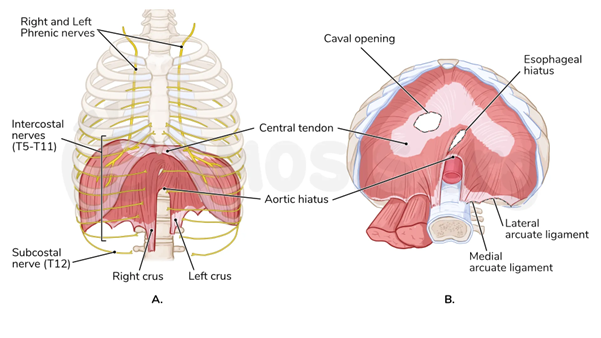

人體天生就是不對稱

根據解剖學的科學文獻及研究,發現人體右側橫膈膜較左側更大、更強壯,且右側附著點在脊椎上較低,這導致右側呼吸與姿勢主導優勢。器官位置(如肝臟偏右、心臟偏左)進一步強化這種不對稱,造成大多數人右腿負重偏好、右側旋轉傾向,並以右胸彎/左腰彎最常見(約佔90%)。